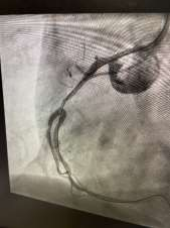

60 year old male known diabetic, hypertensive and dyslipidaemic presented with unstable angina, Coronary angiogram revealed Mid RCA pre crux lesion of 80-90% stenosis and PDA and PLV arising from Mid RCA (Fig 1). It was an angulated bend post bifurcation and hence Fielder FC wire support was taken to easily manipulate the vascular bifurcation (Fig 2) and successful PTCA+ stent to Mid RCA was done with 3x24mm Yukon choice flex stent (Fig 3& 4). TIMI III flow was achieved and post procedure period was uneventful.

FIG 4: Final Shot